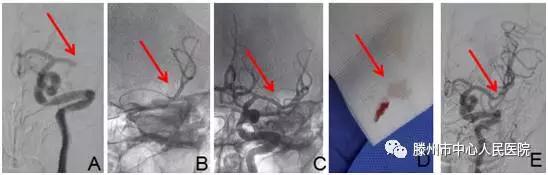

明確診斷為“腦栓塞”后,告知患者家人病情,建議機(jī)械取栓治療。患者家人同意后,急診科護(hù)士迅速護(hù)送病人于9:35分進(jìn)入介入手術(shù)室。再次與患者溝通病情并積極行手術(shù)準(zhǔn)備。9:40股動(dòng)脈穿刺成功,造影見(jiàn)左側(cè)大腦中動(dòng)脈M1段以遠(yuǎn)閉塞(圖A),10點(diǎn)10分支架微導(dǎo)管到位(圖B)

10點(diǎn)19分Soltaire-AB支架到位打開(kāi)后血流恢復(fù)(圖C),患者癥狀明顯減輕,等待5分鐘后,支架取出長(zhǎng)條狀血栓(圖D),患者癥狀完全緩解,言語(yǔ)及肢體力量完全恢復(fù)正常。觀察10分鐘病情無(wú)反復(fù),再次造影左側(cè)大腦中動(dòng)脈顯影完全正常(圖E),結(jié)束手術(shù),安返病房。